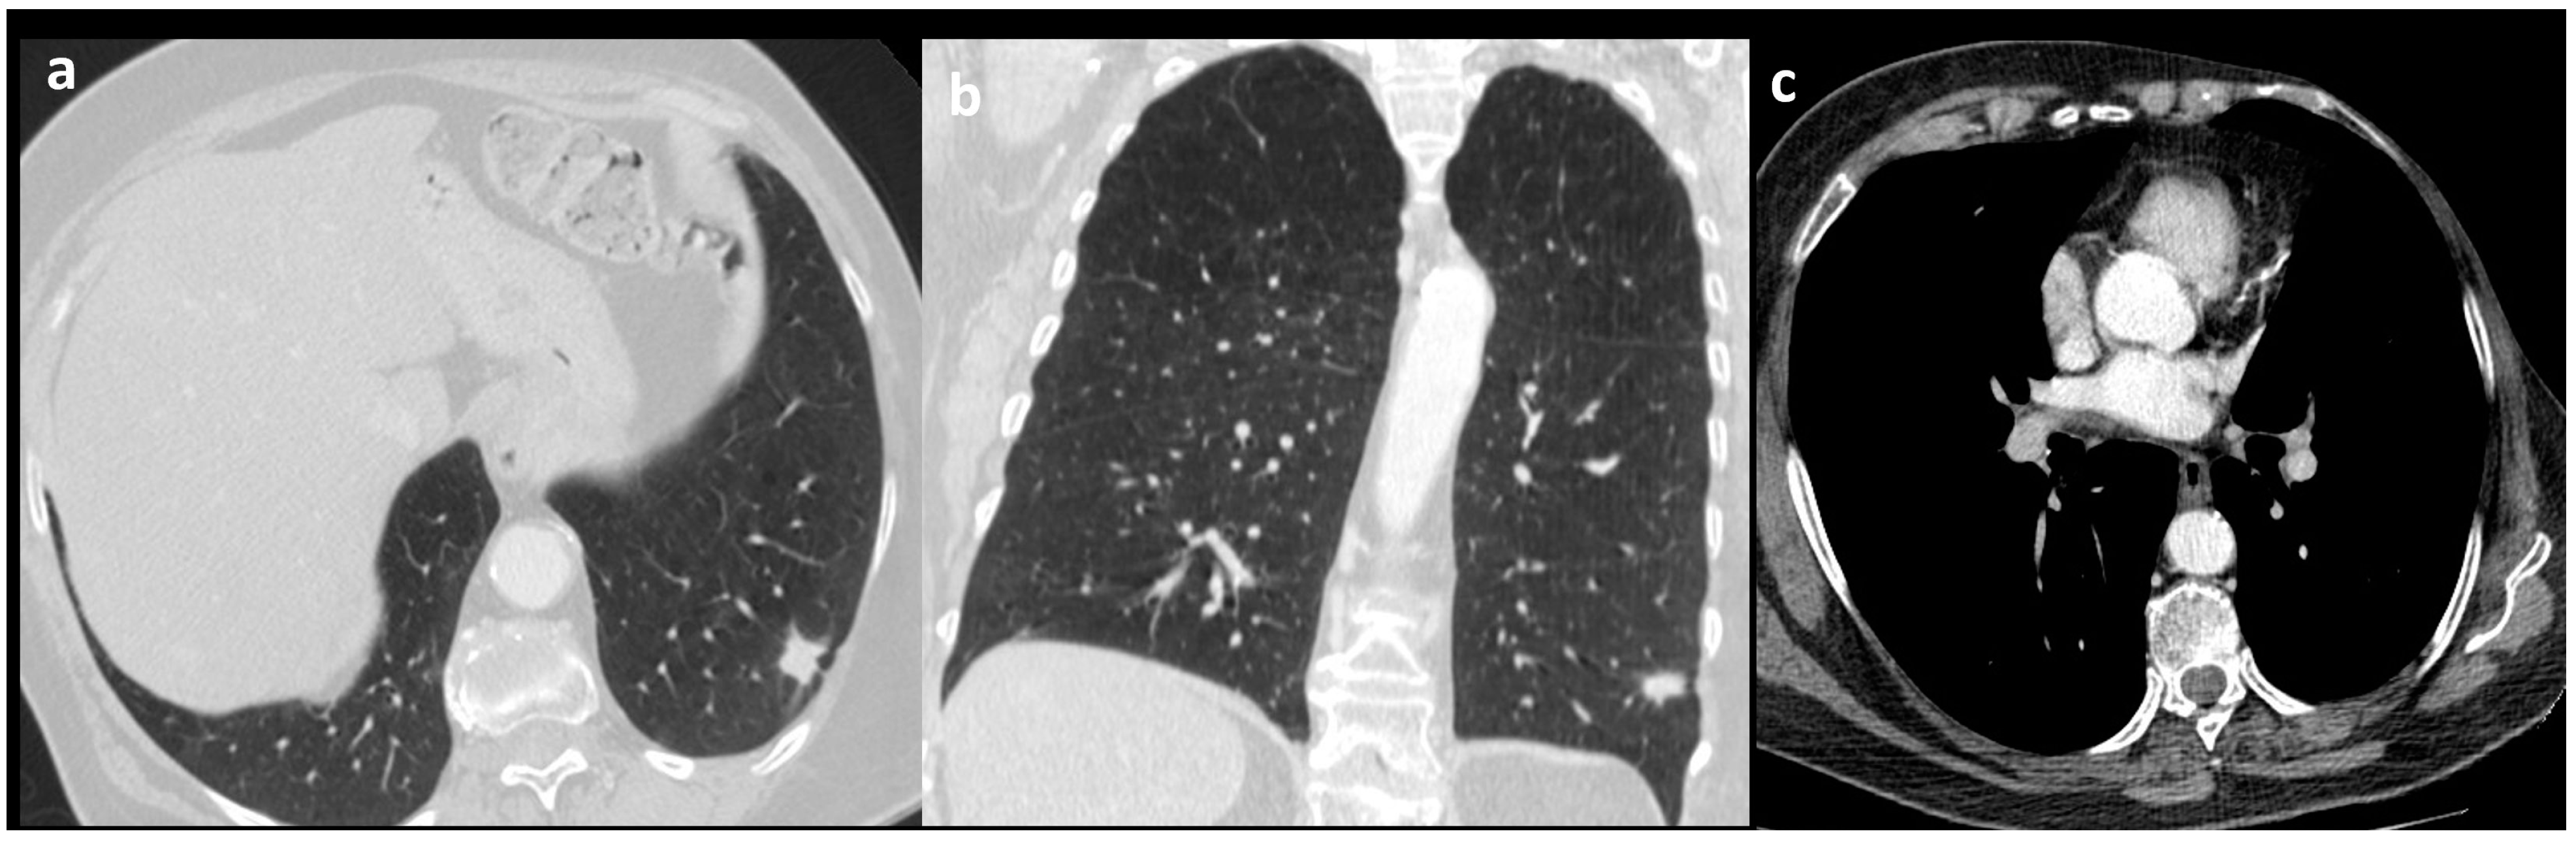

Figure A1. 69 year-old woman patient diagnosed with enteric adenocarcinoma. In the axial (a) and coronal (b) CT images, a spiculated nodule with a pleural tag sign is observed. In the contrast enhanced mediastinal window images (c), a left hilar metastatic lymph node is seen.